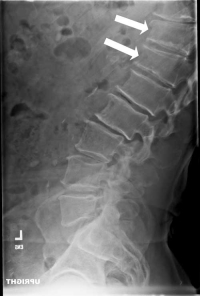

In thoraco-lumbar Scheuermann’s disorder, the anterior growth plates (the front of the vertebra) will fragment and sometimes disappear due to this pressure. This means that while the growth plates in the middle and rear of the vertebra continue to grow, the plates in front stop growing. With this mismatch in growth, the vertebra grows into a wedge instead of a barrel shape creating an abnormal forward angulation called a kyphosis. The normal curve is a backwards curve called a lordosis.

This abnormal curve (the kyphosis) then adds insult to injury. The curve actually increases the load on the front of the spine and creates further overload of the vertebra which in turn worsens the situation similar to a snowball rolling downhill getting bigger the further it rolls.

When the patient with this disorder cause impact to his or her spine (as in landing from a jump), it is not uncommon to have a fracture of the endplate of the vertebra occur. Since the endplate is soft, the jelly in the center of the disc pushes on the endplate and this force produces the fracture. The center jelly actually pushes (herniates) into this cavity which is called a Schmorl’s node.